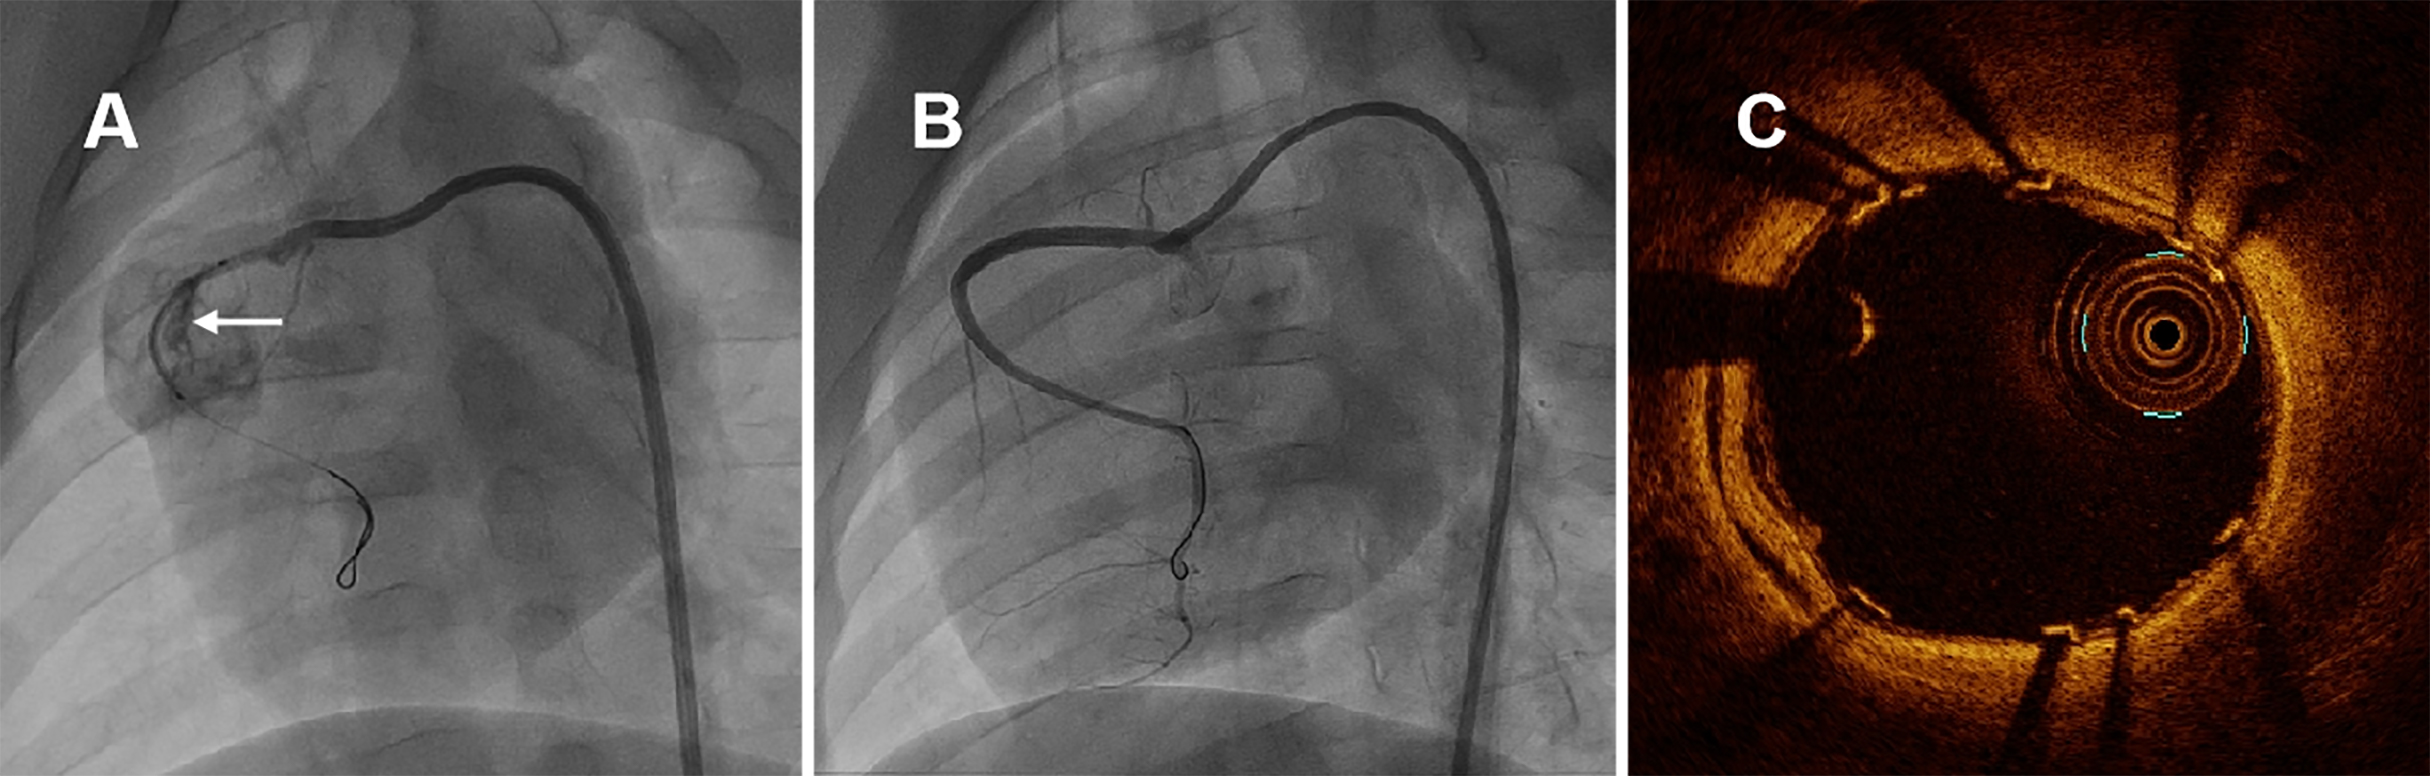

CAG at six months demonstrated total occlusion at the proximal-middle stented RCA segment in all swines, meanwhile with pretty collateral circulation (Rentrop grade 3), shown in Fig. 3E,F and Supplementary Movie 1 and Supplementary Movie 2. Among these animals, two swines were used to constitute occluded stented lesion interventional revascularization and perform the OCT examination. OCT images visualized the diffuse heterogeneous fibrous plaques, as well as organized thrombosis, lipid deposits and several neoatherosclerosis in the occluded segment, shown in Fig. 3A–D and Supplementary Movie 3.

Fig. 3.Representative coronary angiographies and OCT images in swine at six months. (A) Proximal OCT image of the occlusion lesion after interventional recanalization. (B) Proximal-middle OCT image of the occlusion lesion after interventional recanalization. (C) Middle-distal OCT image of the occlusion lesion after interventional recanalization. (D) Distal OCT image of the occlusion lesion after interventional recanalization. Serial OCT images visualized the diffuse heterogeneous fibrous plaques, as well as organized thrombosis, lipid deposits and several neoatherosclerosis in the occluded segment. (E) CAG of RCA in swine at six months, and the white triangle indicated the occluded stented lesion. (F) CAG of LCA in swine at six months, and the white arrow was the collateral circulation. CAG at six months showed total occlusion at the stented segment with pretty collateral circulation. OCT, optical coherence tomography; CAG, coronary angiography; RCA, right coronary artery; LCA, left coronary artery.